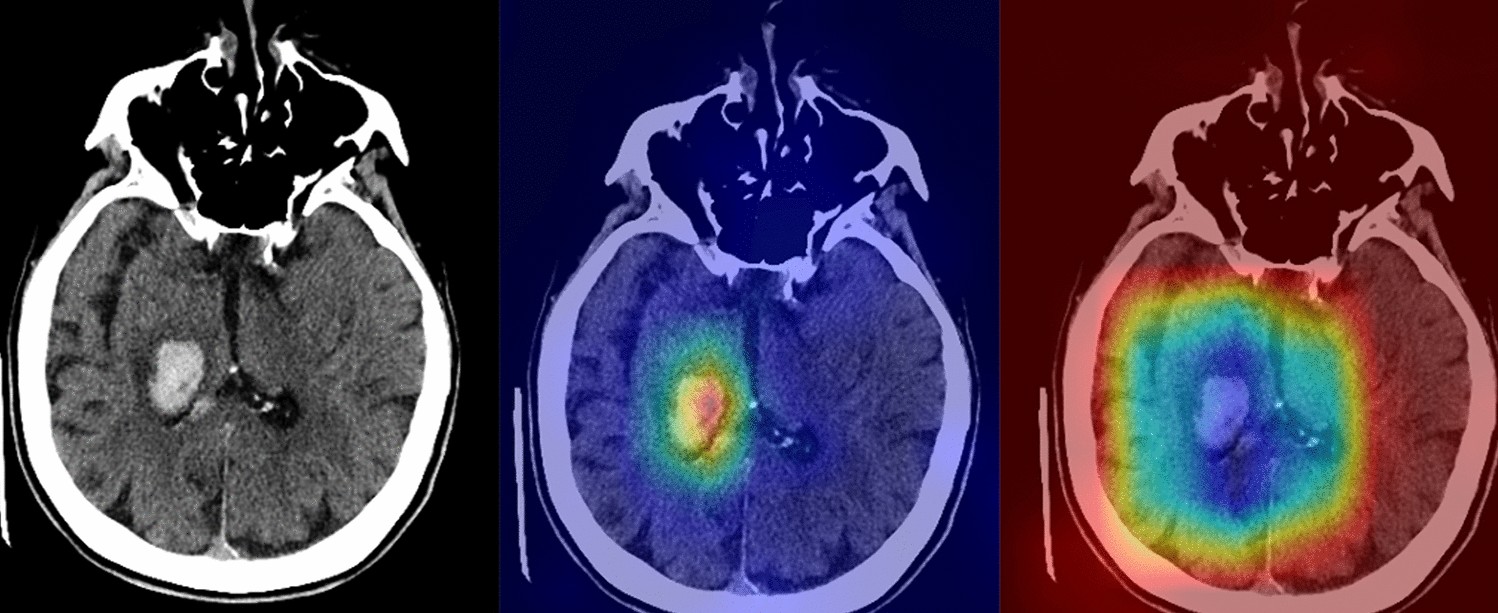

A 68-year-old female with known hypertension (The images were created by the authors using open-source software, Matplotlib v3.5, Python v3). A right thalamic hematoma extended into the adjacent ventricular system on a non-contrast head CT scan (right). NormGrad (middle) method generates more delicate saliency maps than Grad-CAM (left), highlighting the thalamic hematoma and its ventricular extension. The average quality scores were 3.6 points and 2 points for the NormGrad and Grad-CAM, respectively. Please note that the observers evaluated saliency maps with the same color spectrum, and the current color maps are adjusted for representative purposes.